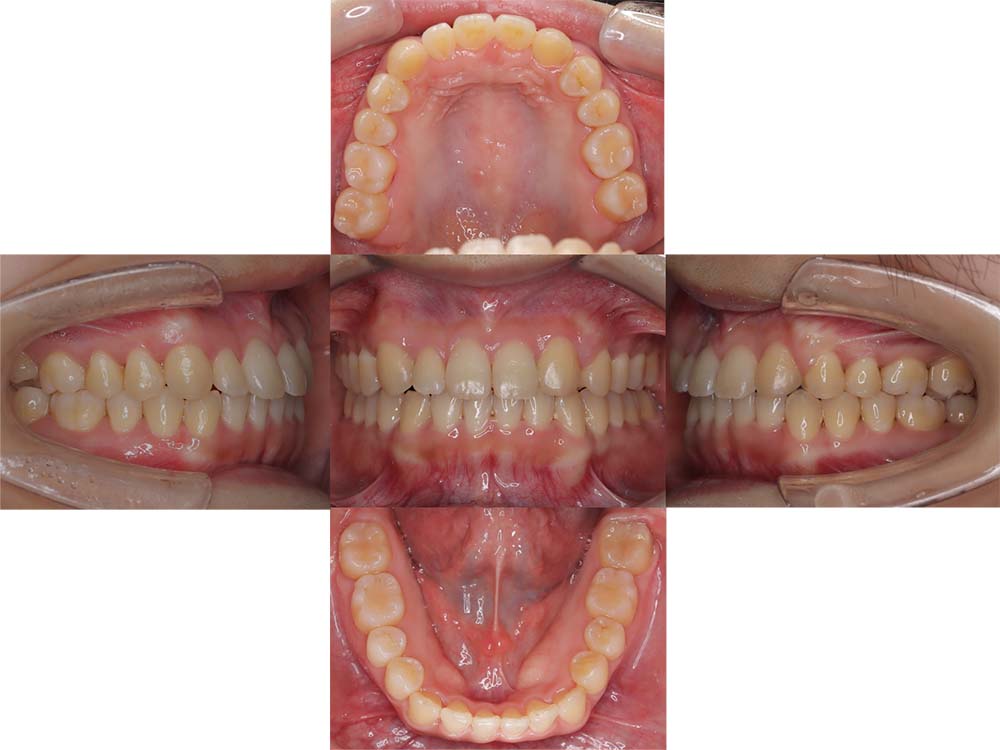

症例04

| 主訴 | 歯並びのガタガタと出っ歯が気になる。 |

| 診断名あるいは主な症状 | 上顎前突、叢生 |

| 年齢/性別 | 16歳・女性 |

| 矯正ステージ | 大人の矯正治療 |

| 治療方法 | ワイヤー矯正 |

| 抜歯部位/抜歯有無 | 抜歯 |

| 治療内容 | 抜歯したスペースを使用し、ガタガタの改善と上下顎前歯を後退させた。 |

| 費用 |

85万円程度(2025.10時点の料金となります。) ※矯正基本料金、審美ブラケットを含む |

| 治療期間 | 2年5ヶ月 |

| 主なリスク・副作用 | 痛み、歯根吸収、歯肉退縮、虫歯、後戻り |